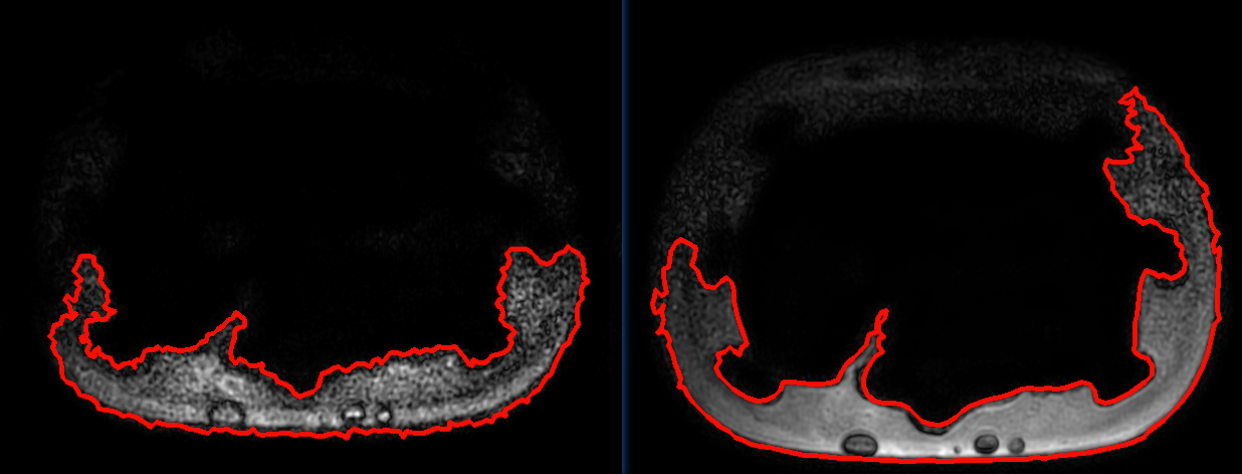

之后还是想着从轴面轮廓开始做,因为其中的操作我明白具体是什么。首先是对原始影像进行预处理,起码得出比较清晰的轮廓。当时想,对于轮廓严重缺失的,直接舍弃,例如下面的轮廓:

对有"轻微凹陷"的轮廓进行修改,像下面这种: